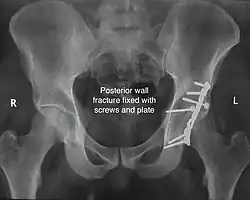

Posterior wall fracture fixed with screws and plate -

The final management depends on the size of the fragment(s), stability and congruence of the joint. In some cases traction for six to eight weeks may be the only treatment required; however, surgical fixation using screw(s) and plate(s) may be required if the injury is more complex. The latter treatment will be called for if bone fragments do not fall into place, or if they are found in the joint, or if the joint itself is unstable.

Innominate bone is a flat bone with many curves. In most part the bone is thick enough and has broad surfaces that are amenable to primary fixation using lag screw(s) and to neutralize forces across the bone one needs to add plate(s) on the surface of the fractured fragments for it to heal without deformity.

Implants : normally lag screws and reconstruction plates are preferred implants